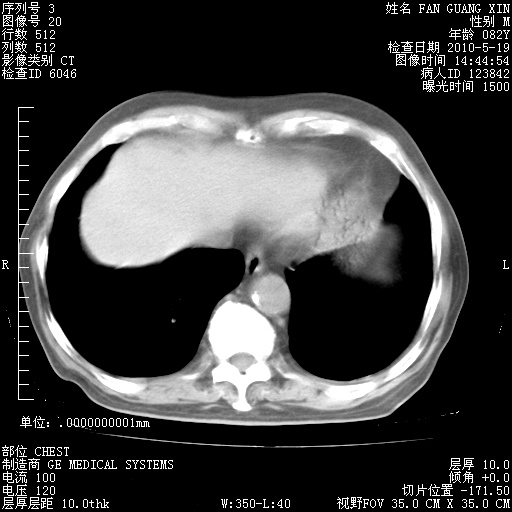

再治疗10天后的肺部CT 纵膈窗

阅读此次胸部CT,肺间质渗出性改变较入院时有吸收。目前从体温、白细胞、中性分叶明显增高,肯定存在细菌感染(发生医院感染哦,若无消化道及泌尿系统等感染的依据,肺部感染可能大)。若你院头孢哌酮舒巴坦钠耐药率较高,同意你的方案,若48小时体温仍高,可考虑使用碳青霉稀类抗菌药物,同时可予超声雾化、注意滴数时加大液体量。白蛋白33.30g/L较低哦,需加强营养等支持治疗。